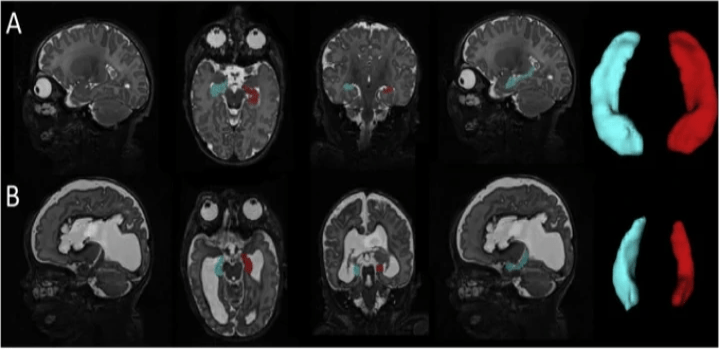

Impaired hippocampal development and outcomes in very preterm infants with perinatal brain injury

Neuroimage Clin. 2019; 22: 101787.

Preterm infants are at high risk for brain injury during the perinatal period. Intraventricular hemorrhage and periventricular leukomalacia, the two most common patterns of brain injury in prematurely-born children, are associated with poor neurodevelopmental outcomes. The hippocampus is known to be critical for learning and memory; however, it remains unknown how these forms of brain injury affect hippocampal growth and how the resulting alterations in hippocampal development relate to childhood outcomes. To investigate these relationships, hippocampal segmentations were performed on term equivalent MRI scans from 55 full-term infants, 85 very preterm infants (born ≤32 weeks gestation) with no to mild brain injury and 73 very preterm infants with brain injury (e.g., grade III/IV intraventricular hemorrhage, post-hemorrhagic hydrocephalus, cystic periventricular leukomalacia). Consistent with our preclinical findings, these findings demonstrate that perinatal brain injury is associated with hippocampal size in preterm infants, with smaller volumes related to domain-specific neurodevelopmental impairments in this high-risk clinical population.